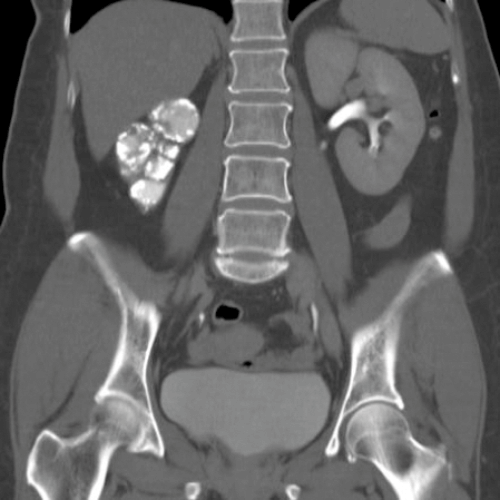

Figure 2b.

- Figure 2 shows other radiological features of one of these possible causes. What is the likely diagnosis? How often does this condition affect the urinary tract?

-

TB, 15% genitourinary tract involvement. A: left autonephrectomy, B: non-functioning right kidney with left sided infundibular scarring and caliectasis, left distal ureteric stricture, small capacity bladder.

Kidney (haematogenous spread): infundibular stenosis and calyceal dilatation, papillary necrosis, ‘putty’ kidney, autonephrectomy. Ureter: lower ureteric strictures, gold hole ureteric orifice. Bladder: ‘thimble’ bladder, calcification, reduces capacity. Rarer: prostatitis, urethritis, epidydmitis (string of beads), orchitis.

Renal calcification, infundibular stenosis, autonephrectomy, ureteric calcification / strictures, calcified bladder, small volume bladder.